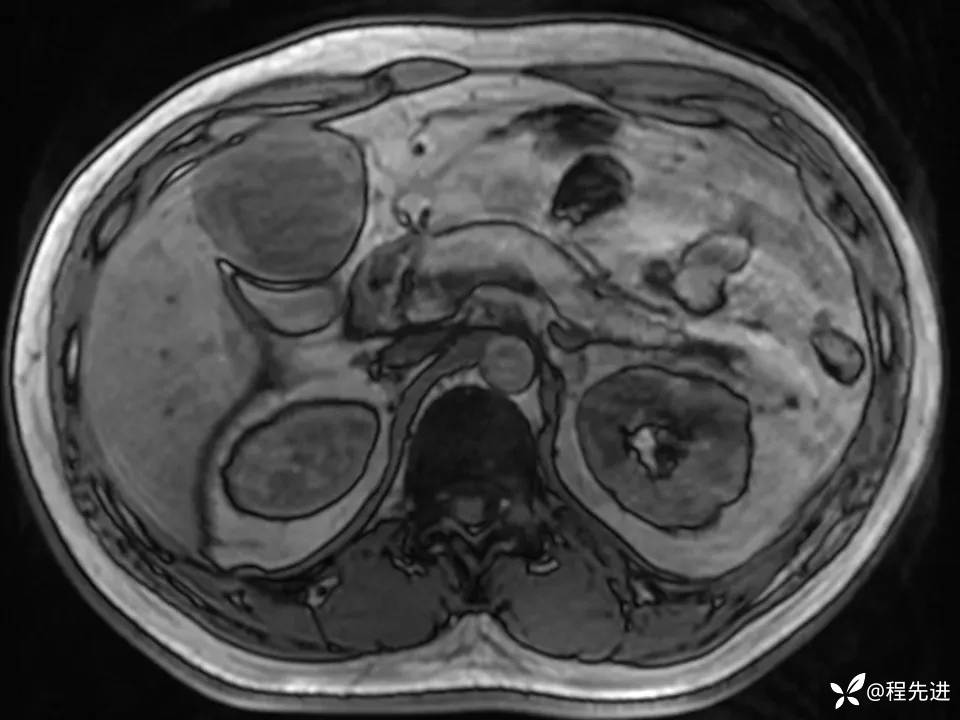

患者性别:男

患者年龄:27岁

简要病史:体检发现肝脏占位2周

既往史:平素体健,无特殊

实验室检查:(-)